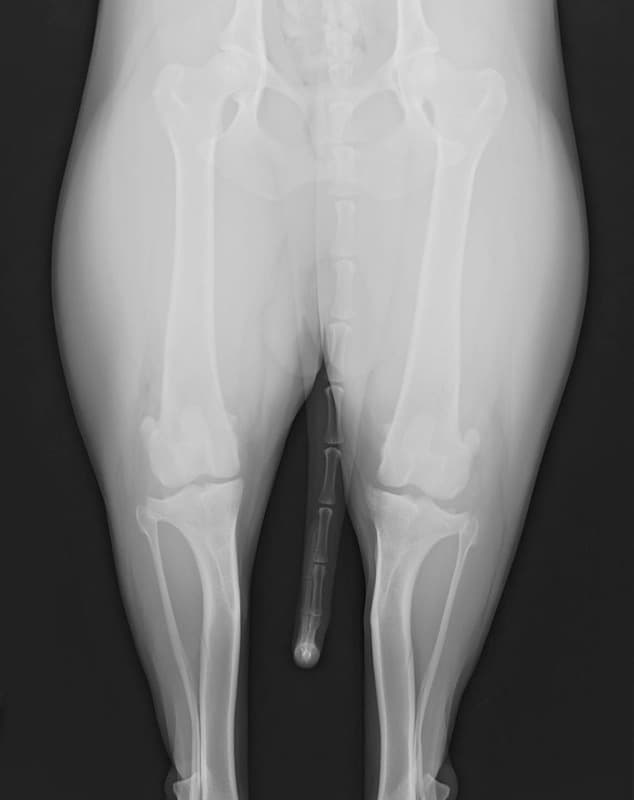

左後肢の挙上を主訴に来院されました。触診にて両関節の前方引き出し兆候、両膝蓋骨の内方脱臼を認めました。関節液検査より免疫介在性多発性関節炎は否定的でした。レントゲン検査にてfat pad signを伴う関節炎が認められたことから、前十字靭帯断裂と膝蓋骨内方脱臼(左GradeⅢ 右GradeⅢ〜IV)併発と診断し、手術を行いました。

術前正面像